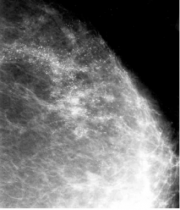

| 16:20, 5 בספטמבר 2012 | Breastcancer2512.png (קובץ) |  |

107 קילו־בייטים | Motyk | 1 | |